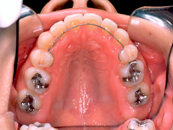

叢生 治療前 上顎

この患者さんでは、上下左右の歯を計4本抜きましたが、それでももスペースが足りませんので、さらに顎の形を変えて並べ替えました。

抜歯する歯は、変なところに生えていた犬歯ではなく、4番目の歯(=第一小臼歯)です。犬歯を抜くと、顎運動や歯並びの見た目、口元のふくらみがなくなることで老けて見えるなど、いろいろな悪影響があります。従って、できるだけ抜歯は避けたいのです。

歯を抜いたスペースを利用して、残りの歯をきれいに並べ替えてゆきます。この患者さんの場合は、抜いたスペースはほとんど余りませんので、意外に早く治療が終わりました。